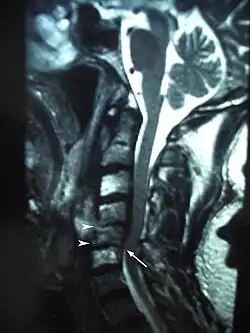

MRI showing osteoradionecrosis in the cervical vertebrae following radiotherapy for laryngeal cancer.